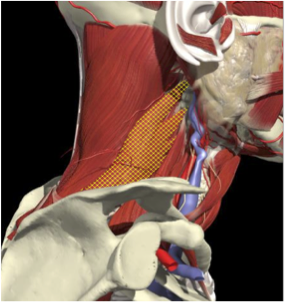

ACCURACY OF LOCALIZATION - SCALENES

ACCURACY OF LOCALIZATION LEVATOR SCAPULAE

LOCALIZATION OF MUSCLES IN DEEPER LAYERS

Layer 1

Layer 2

Layer 3

Splenius Capitis

Semispinalis Capitis

Longissimus Capitus

Semispinalis Cervicis

ACCURACY OF LOCALIZATION – DEEPER LAYERS

INJECTION SITES